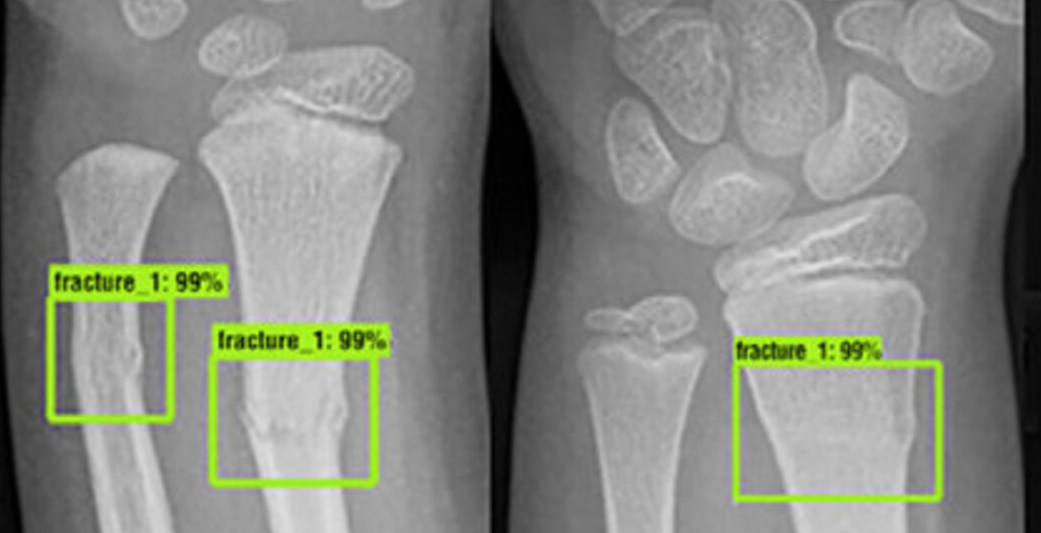

Bone Fracture Detection

Our AI-powered system quickly identifies bone fractures in X-ray images, helping orthopedic surgeons make faster and more accurate diagnoses.

Bone Fracture Image